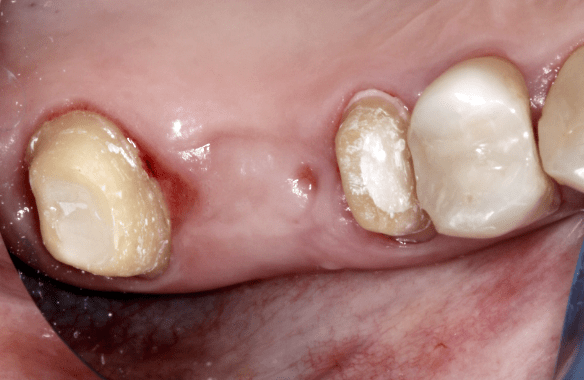

Dr. Sápi Béla páciense a hiányzó jobb felső első nagyőrlőjét szerette volna pótoltatni, és a szakvéleményt figyelembe véve a hídpótlás mellett döntött. A fémkerámia pótlások esetében egy belső kobalt-króm ötvözet adja a belső, merev vázat, amely cementtel rögzül a fogra (vagy a fogakra), és erre kerül ráégetéssel az esztétikus, fogszínű kerámia. A fémkerámia pótlás előnye, hogy költségkímélőbb a többi pótlással szemben, és ezzel a hagyományos módszerrel is tartós és esztétikailag kielégítő pótlások készíthetőek.

Bár a pótláshoz megoldásképpen akár az implantáció is szóba jöhetett volna, a vizsgálatokból és a röntgenfelvételekből az derült ki, hogy az implantátum behelyezéséhez az alacsonyan elhelyezkedő arcüreg miatt csontpótlásra (sinus-liftre) is szükség lett volna. Ezt megfontolván a páciens inkább a hídpótlás mellett döntött.

A foghiányt közrefogó fogakat előkészítettük (lecsiszoltuk) a hídpótláshoz.